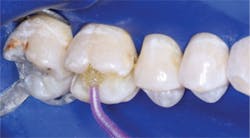

- Place the restorative resin in increments, starting with 0.5 mm in the deepest portion of the box form, increasing to 1.0 mm and finally to 2.0 mm increments. Clinicians Report research has shown that currently popular curing lights do not cure the entire depth of a typical box form at 7 mm.

- Finish and polish the restoration.